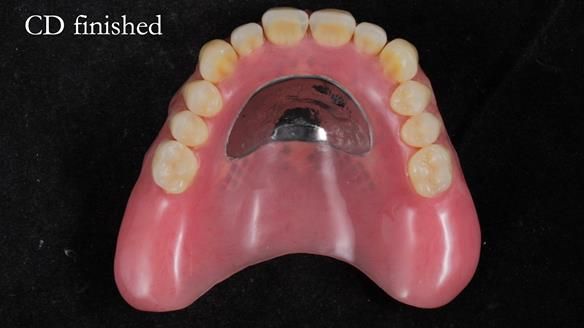

The detailed clinical situation and treatment process are outlined below, with clinical work provided by me and technical work by Rowan Garstang. The treatment spanned 12 months, involving removing 5 upper anterior teeth, adding to an existing upper RPD, followed by creating and fitting metal based complete dentures.